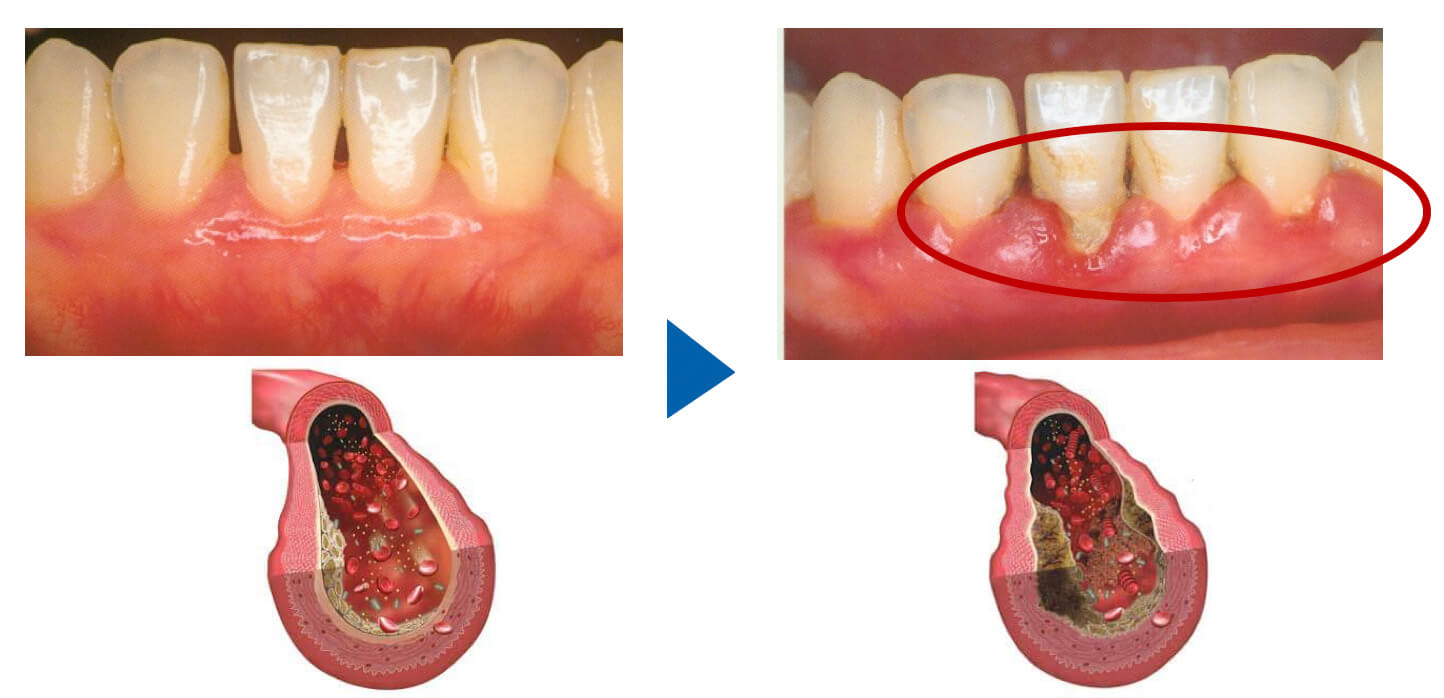

歯周病菌が歯茎の血管に入り込み、70秒後には手の指先に到達。全身を巡りながら様々な炎症を引き起こします。

動脈硬化などの原因に。また、歯を失うと、血管の老化にもつながります。

歯周病菌

この細菌たちは、お口の中で炎症や傷口があったり、食事をすることで体内に入り、血管内を泳ぎ、全身に廻ります。(他人にも感染します)